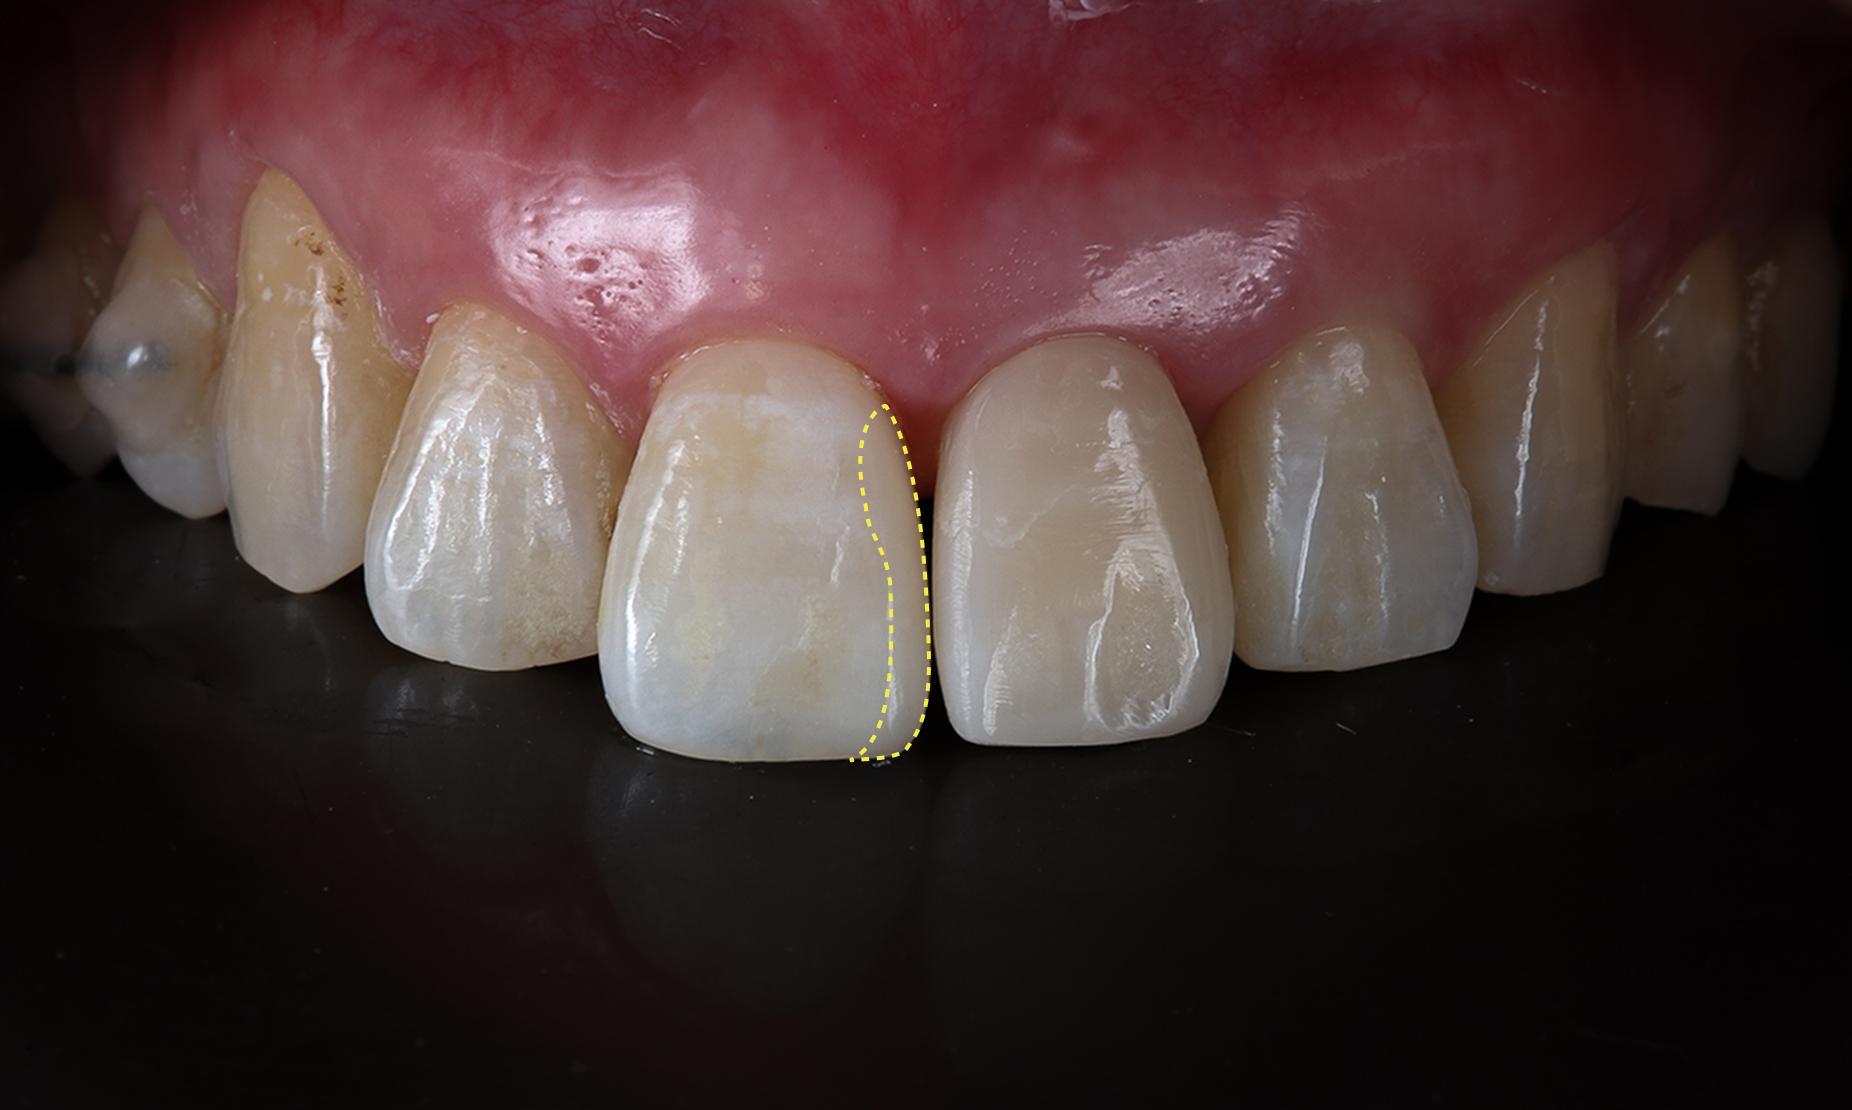

並行して、隣接する健康な歯にダイレクトボンディングで幅を足し、左右対称の歯列を作り上げました。

ダイレクトボンディングによる横幅の調整を行いました。

前後を比べるとシミュレーション通り明らかに歯幅が増えている。